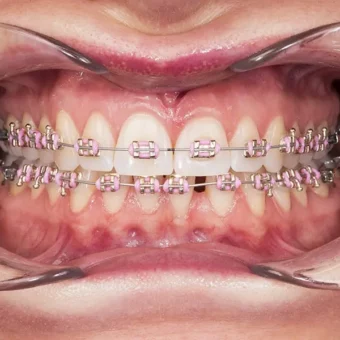

Druga wizyta w naszej klinice to czas na dokładne badania oraz diagnozę. Wykonujemy wtedy sesję zdjęciową – portretową oraz wewnątrzustną. Na podstawie tych materiałów dokonywana jest bardzo staranna analiza oraz projektowanie uśmiechu. Kolejny krok to zrobienie wycisków oraz przeprowadzenie rejestracji zgryzu. Jako jedna z nielicznych klinik w Polsce, Sobota House of Dentistry wprowadziła standardowo do procesu leczenia diagnozę mięśni i stawów pod kątem choroby okluzyjnej. Ta wiedza pozwala przeciwdziałać nawrotom wad zgryzu po kilku latach dzięki osiągnięciu idealnej harmonii zębów i stawów skroniowych. Dodatkowo eliminuje przyczyny i leczy objawy choroby okluzyjnej jakimi są m.in. ścieranie i zgrzytanie zębami, bóle w stawach skroniowo-żuchowwych, a nawet bóle głowy.

Podczas leczenia Pacjent jest pod stałą opieką nie tylko ortodonty, ale także profesjonalnej dyplomowanej higienistki, która dba o czystość zębów z aparatem ortodontycznym. Higienistka indywidualnie dobiera środki do higieny i metody oczyszczania zębów. Dodatkowo przeprowadza regularne fluoryzację zębów tak, aby zęby po zdjęciu aparatu były piękne i bez odbarwień.

Aparaty stałe

Są to systemy mocowane do zewnętrznych powierzchni zębów. Stosowane zamki ortodontyczne wykonane są z metalu. Zamki te nie niszczą szkliwa zębów, a ich rodzaj dostosowujemy do indywidualnych potrzeb Pacjenta. Popularne systemy:

- cienkołukowe (samoligaturujące i ligaturujące)